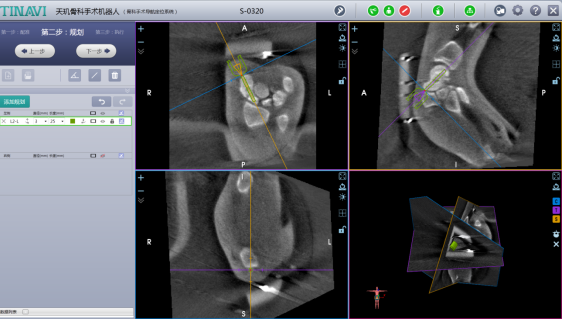

术中机器人导航